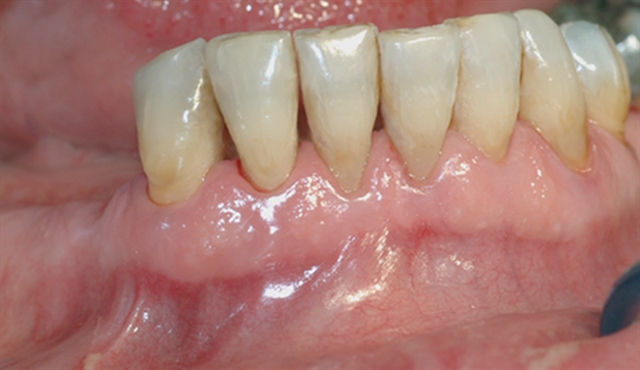

• Biletet viser tilsynelatande normale tannkjøttilhøve ved tenner i underkjeven.

• Biletet viser eit nærbilete av tennene i underkjeven med tannstein og misfarging.